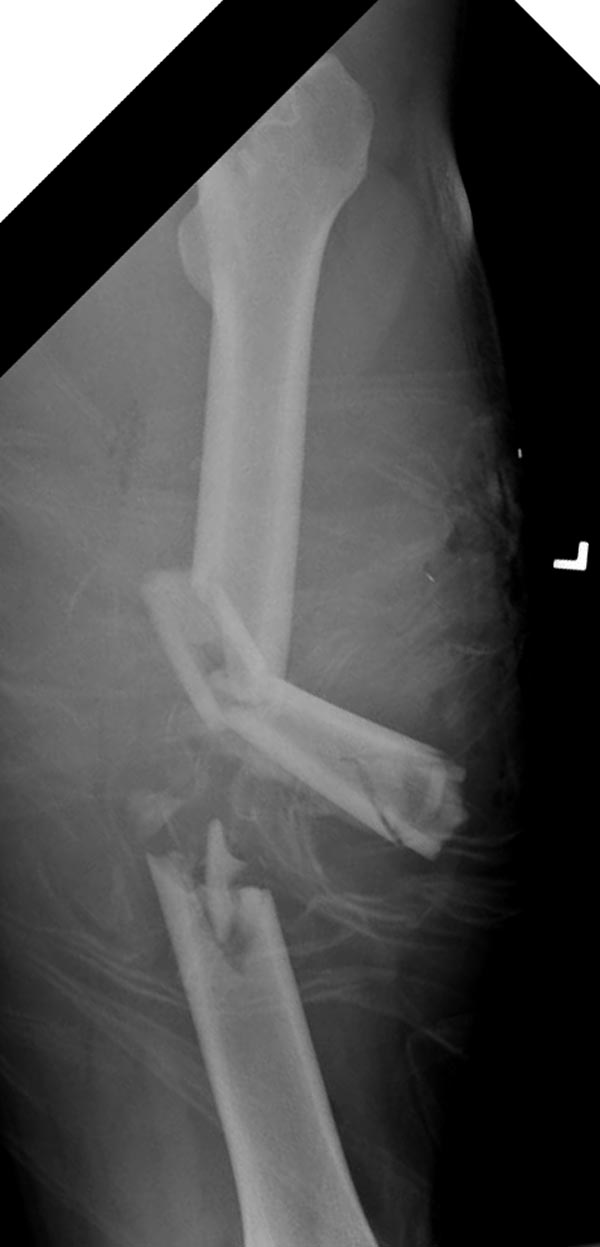

Здесь выставлен ренгенограммы больного, ему 21, травму получил в

результате высокоскоростной погони на украденной машине, которая

закончилась смертью трех остальных“боевых комрадов”. Начатую коллегой

открытую операцию на шейке пришлось закончить мне, установкой винтов и

ретроградной фиксацией бедра. Выписка в обычное сроки и наблюдался